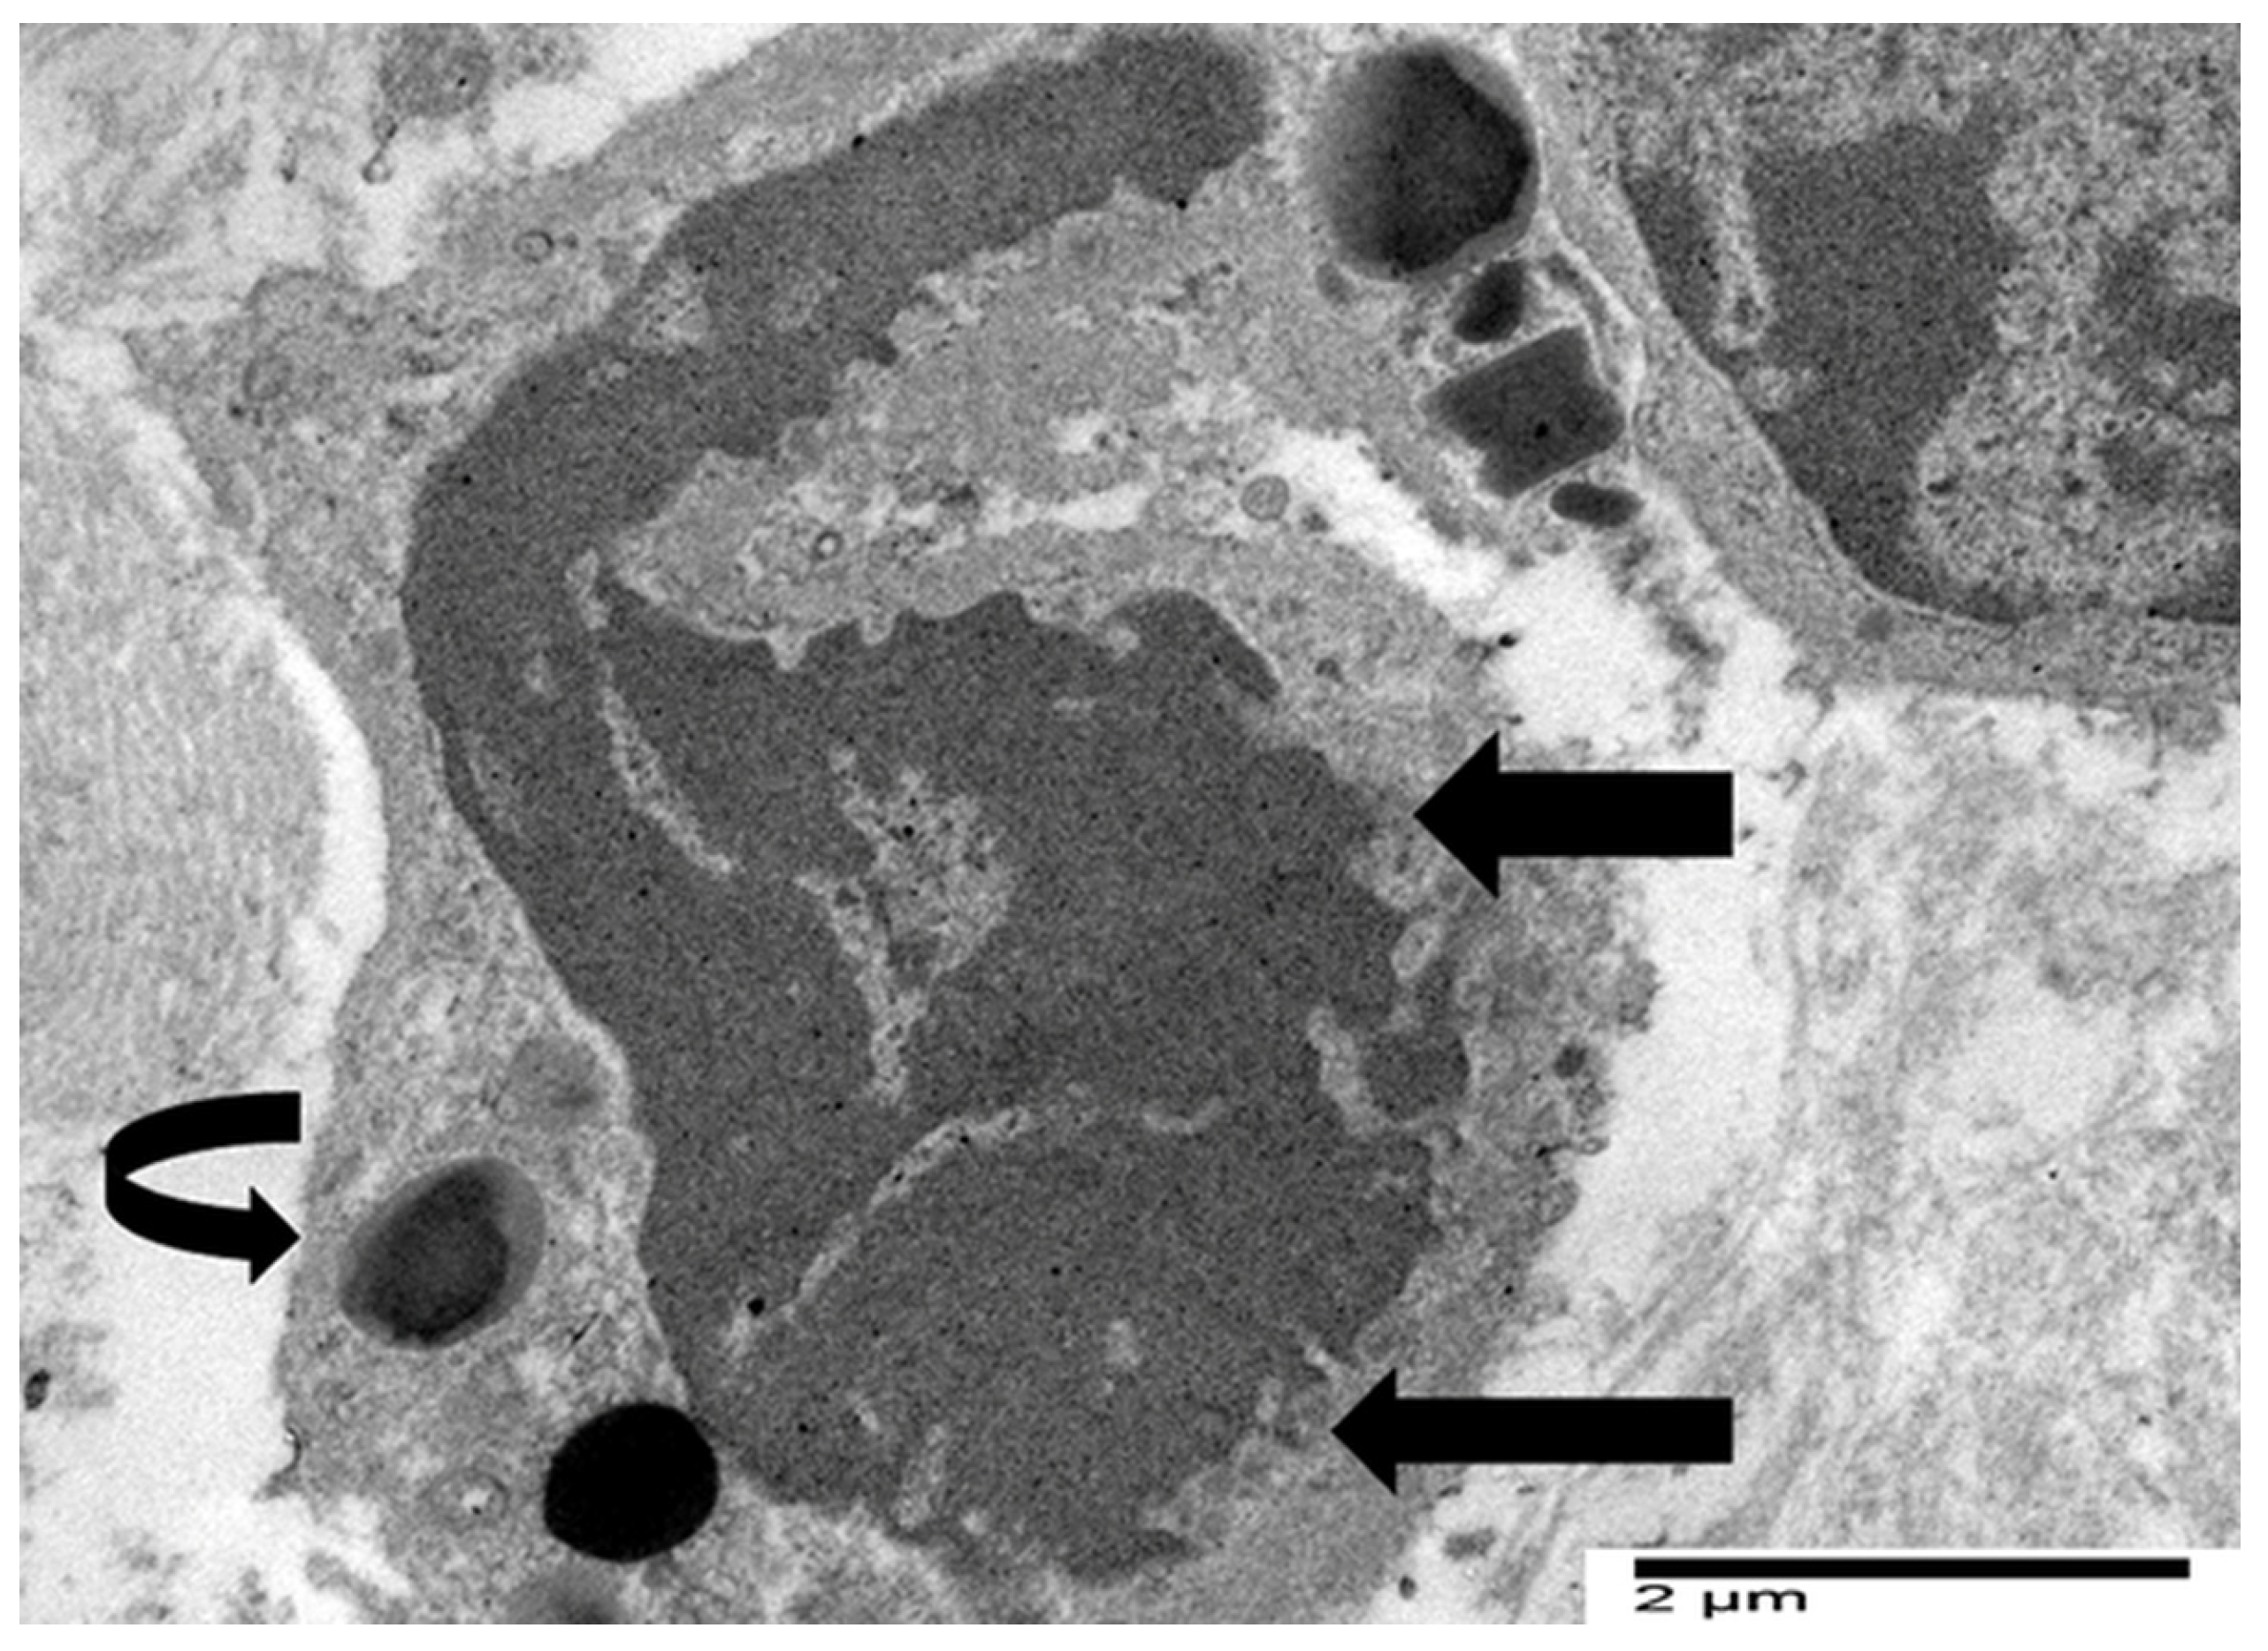

4.3. Our Ultrastructural Observations of Eosinophil ETosis in Gastric Carcinoma

5.2. Ultrastructural Evidence of Eosinophil-Mediated Tumor Cell Injury in Gastric Carcinomas

- Neves, V.H.; Palazzi, C.; Bonjour, K.; Ueki, S.; Weller, P.F.; Melo, R.C.N. In Vivo ETosis of Human Eosinophils: The Ultrastructural Signature Captured by TEM in Eosinophilic Diseases. Front. Immunol. 2022, 13, 938691. [Google Scholar] [CrossRef]

- Caruso, R.; Caruso, V.; Rigoli, L. Ultrastructural evidence of eosinophil clustering and ETosis in association with damage to single tumour cells in a case of poorly cohesive NOS gastric carcinoma. Eur. J. Case Rep. Intern. Med. 2023, 10, 004016. [Google Scholar] [CrossRef]

- Caruso, R.; Caruso, V.; Rigoli, L. Eosinophil cytolysis with or without ETosis in four cases of human gastric cancer: A comparative ultrastructural study. Explor. Target. Antitumor Ther. 2025, 6, 1002309. [Google Scholar] [CrossRef]